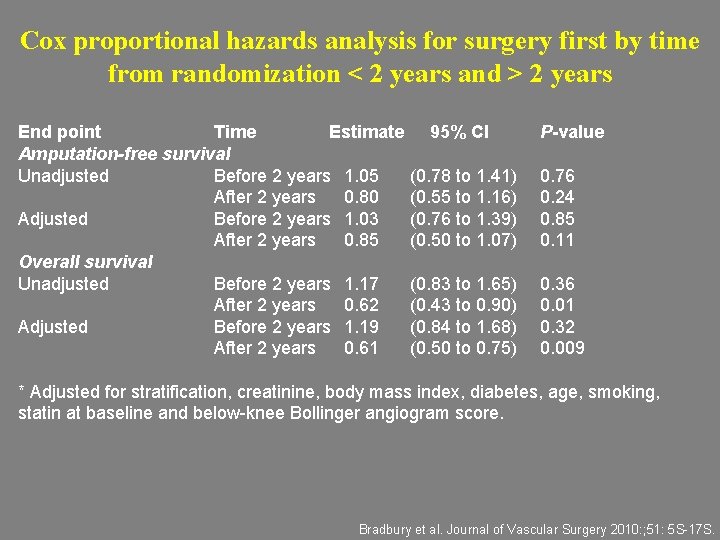

Cox proportional hazards analysis for surgery first by time from randomization < 2 years and > 2 years End point Time Estimate Amputation-free survival Unadjusted Before 2 years 1. 05 After 2 years 0. 80 Adjusted Before 2 years 1. 03 After 2 years 0. 85 Overall survival Unadjusted Before 2 years 1. 17 After 2 years 0. 62 Adjusted Before 2 years 1. 19 After 2 years 0. 61 95% CI P-value (0. 78 to 1. 41) (0. 55 to 1. 16) (0. 76 to 1. 39) (0. 50 to 1. 07) 0. 76 0. 24 0. 85 0. 11 (0. 83 to 1. 65) (0. 43 to 0. 90) (0. 84 to 1. 68) (0. 50 to 0. 75) 0. 36 0. 01 0. 32 0. 009 * Adjusted for stratification, creatinine, body mass index, diabetes, age, smoking, statin at baseline and below-knee Bollinger angiogram score. Bradbury et al. Journal of Vascular Surgery 2010: ; 51: 5 S-17 S.